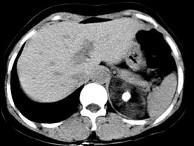

问题 男性,28岁,左腰背酸胀5个月,CT检查如图所示,应诊断为()

选项 A.左肾上腺髓样脂肪瘤 B.左肾上腺错构瘤 C.左肾上腺嗜铬细胞瘤 D.左肾上腺腺瘤 E.左肾上腺转移瘤

答案 B